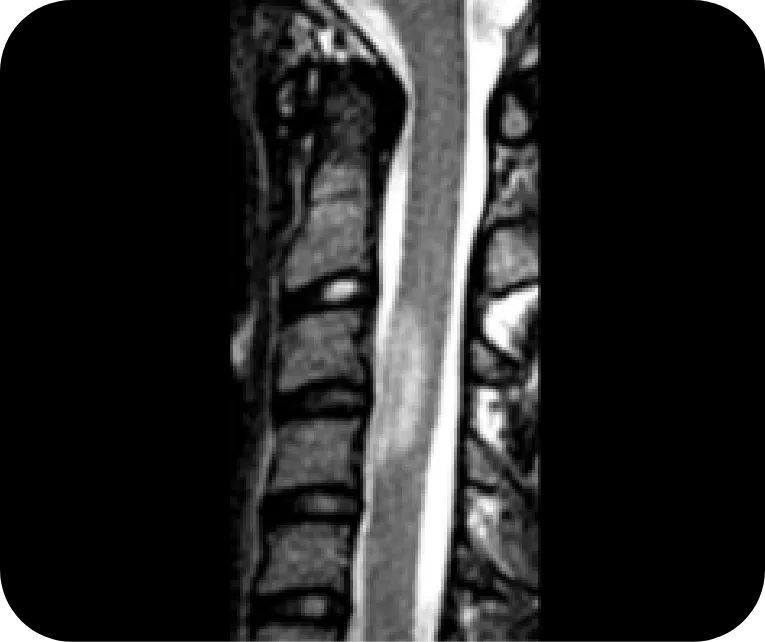

Cervical Spine

NMOSD

Longitudinally extensive transverse myelitis, characteristic of NMOSD, extending into the area postrema

Reprinted with permission from Radiographics, 2018;38(1):169-193. ©RSNA

MS

Ovoid and longitudinally short lesions typical of MS myelitis